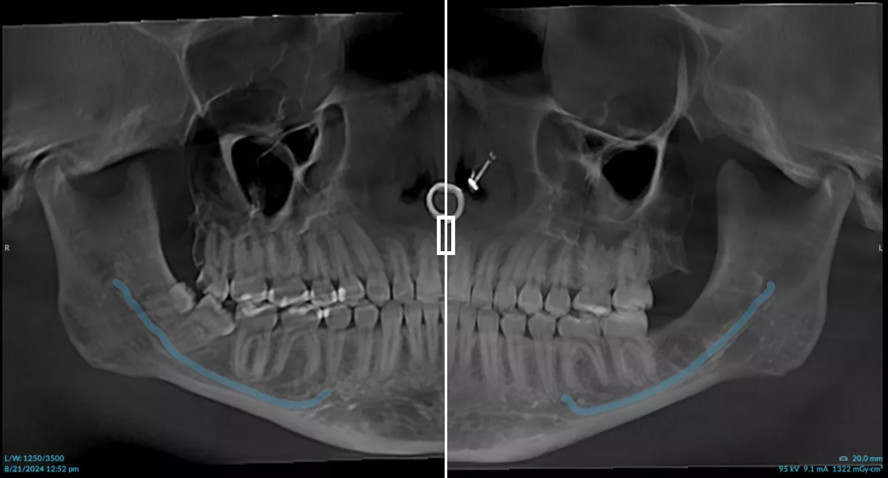

Bei einem anderen Patienten zeigte die automatische Dosissteuerung bilaterale Verkalkungen der Halsschlagader, was auf die mögliche Notwendigkeit einer beidseitigen Carotis-Endarteriektomie hinweist. „Die Verkalkung ist auf dem Bild deutlich zu erkennen“, erklärt er. „Man kann sie sowohl an der medialen als auch an der lateralen Wand deutlich sehen, sodass ich diesem Patienten raten konnte, mit seinem Arzt über das Problem zu sprechen, da ein erhöhtes Risiko für einen Schlaganfall oder einen anderen Notfall besteht.“